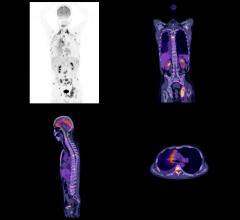

Radiation oncology is a medical specialty that uses radiation therapy to treat cancer. The radiation therapy channel covers all aspects of radiation oncology technology. Radiation therapy includes linear accelerators (LINAC), proton therapy, brachytherapy, image guided radiation therapy (IGRT), focused ultrasound, stereotactic body radiation therapy (SBRT), intensity modulated radiation therapy (IMRT), treatment planning systems and tomotherapy.